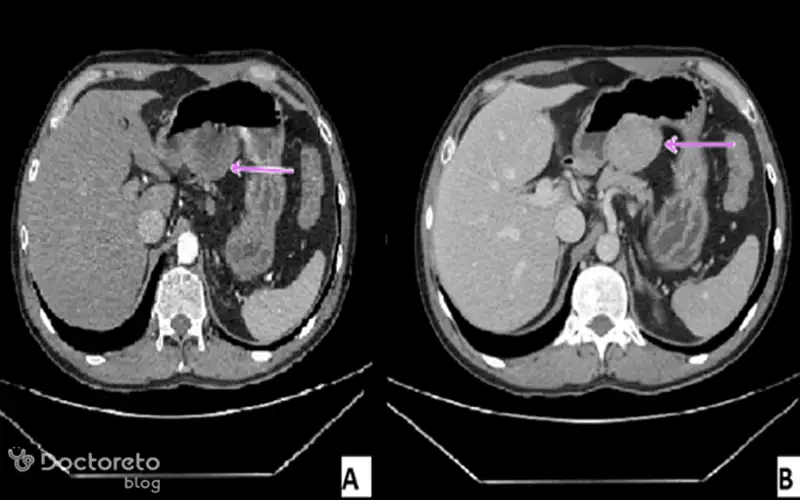

عکس سی تی اسکن سرطان معده خوش خیم

سیتیاسکن ابزار قوی دیگری برای ارزیابی تومورهای معده است. این روش تصویربرداری به ویژه در تشخیص اندازه، موقعیت و ارتباط آنها با ساختارهای اطراف کاربرد دارد. حتی برای سلولهای خوشخیم سرطانی هم سیتیاسکن اطلاعات ارزشمندی در مورد چگونگی رشد و وضعیت بیمار ارائه میدهد. استفاده از این تصاویر کمک میکند تا پزشک نگاهی دقیقتر به تومور معده داشته باشد.